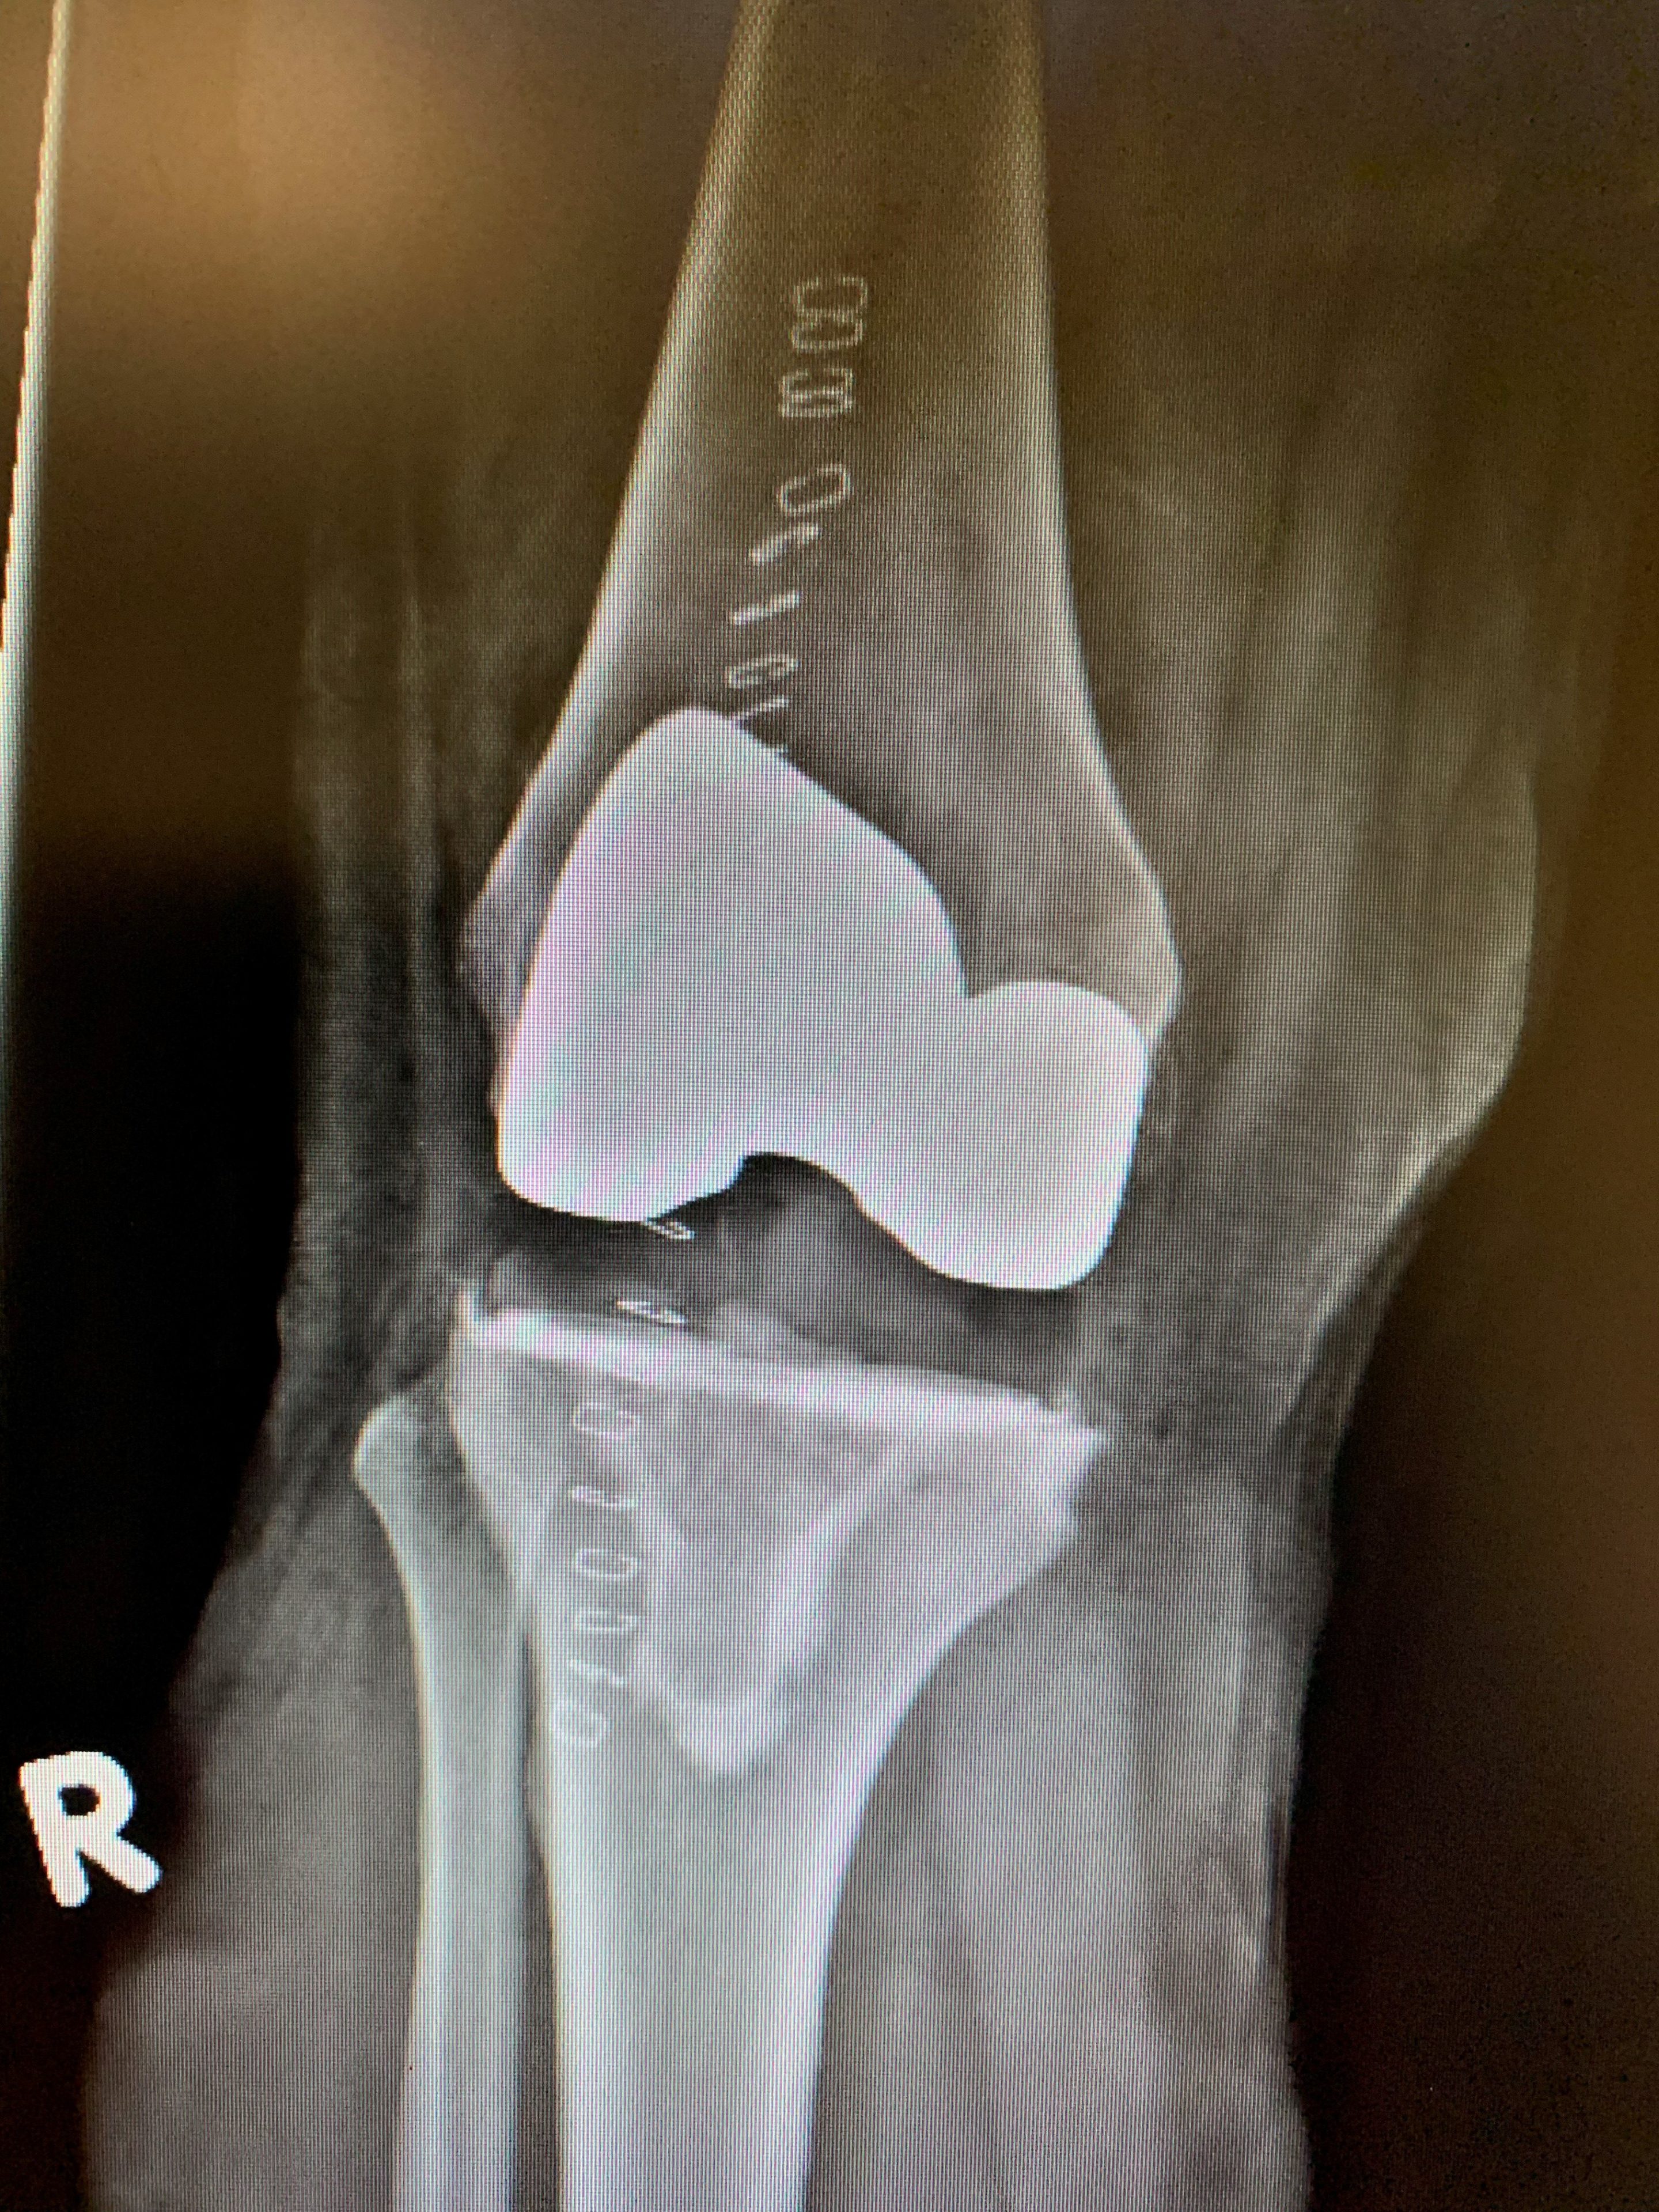

Su examen de rodilla no fue notable, aunque estaba visiblemente incómoda durante el mismo. Sus radiografías revelan osteoartritis en varo con enfermedad posterior significativa en comparación con más anterior.

Completamos su reemplazo de rodilla con la ayuda del sistema de navegación por computadora. Se recuperó bien y salió del hospital el día después de su cirugía.

Postoperatorio